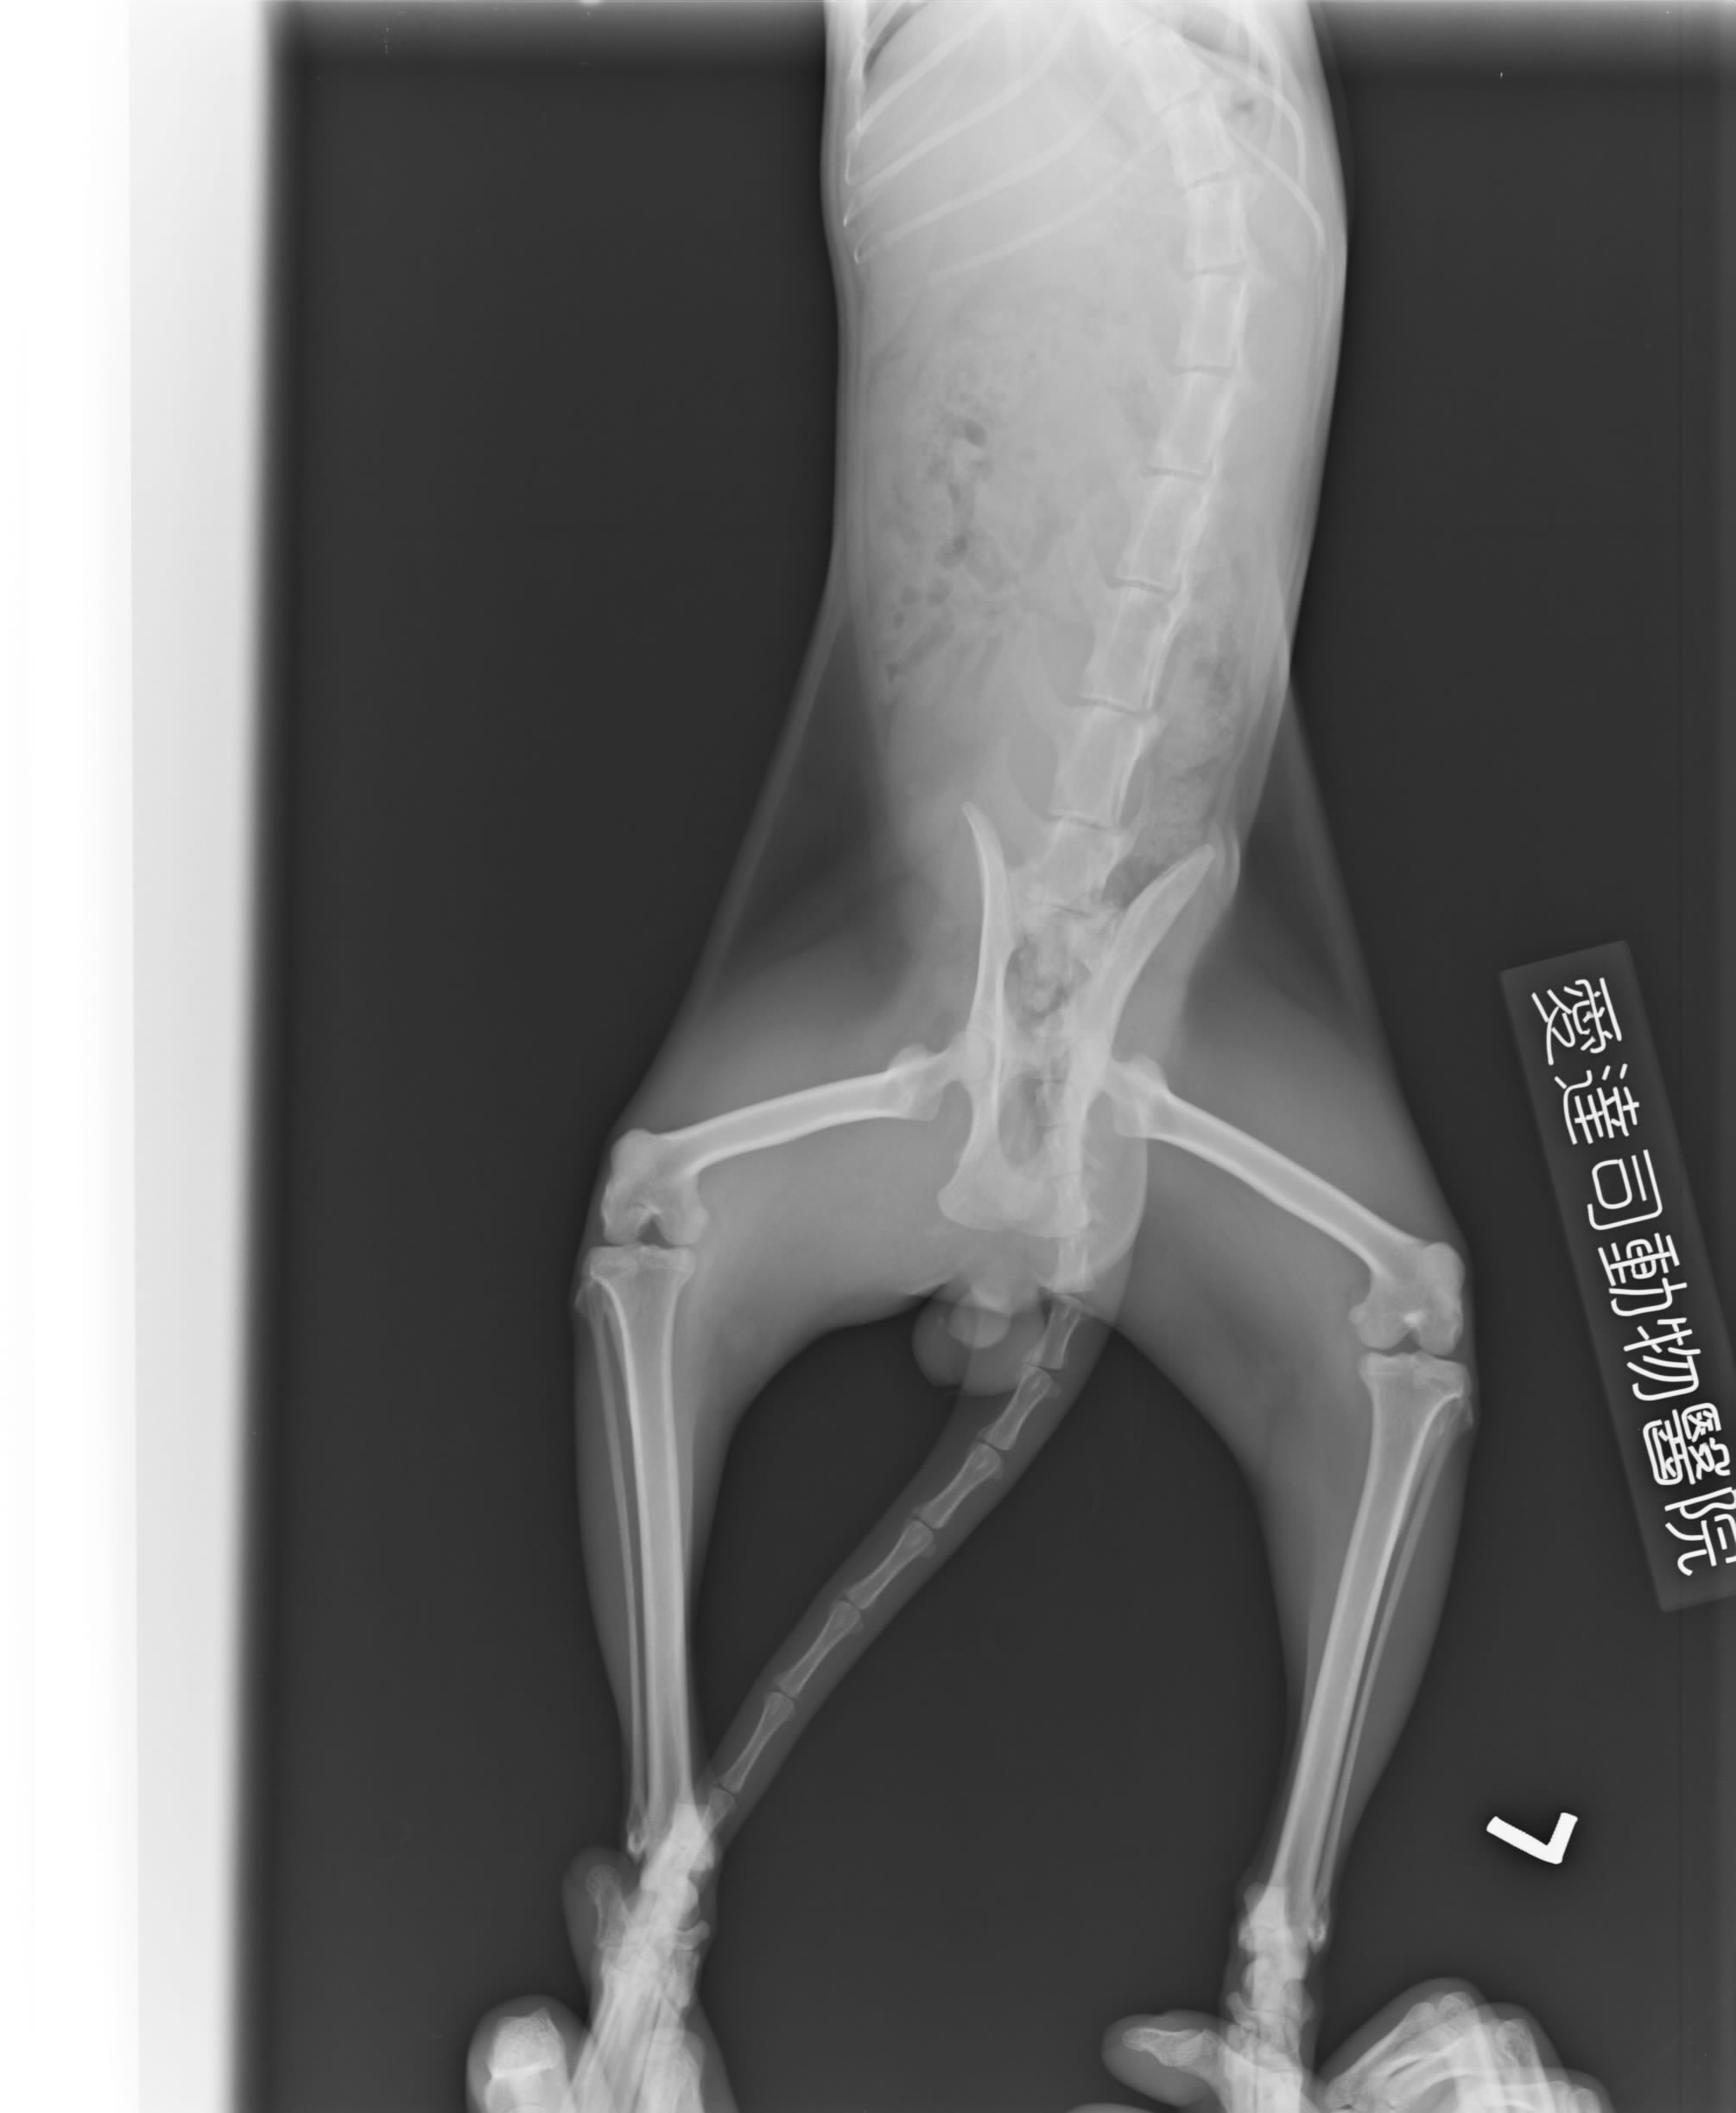

主題: 三峽疑似車禍骨盆骨折的孩子 申請者姓名: 李欣羽 花色: 申請日期: 2012-12-03 04:22:08 申請者部落格: 申請者臉書網址: a714814@yahoo.com.tw 所在縣市/合作醫院: 新北市/愛達司動物醫院 治療費用: 6500元 需求人數: 15人 已結案 (2013-06-27 14:08:48) 報名人員: Chi Kang Yang(已付款)、Deb Lan、Deb Lan(已付款)、Coco Ho(已付款)、banana huang(已付款)、Piano Chiu(已付款)、李宜珊、Kay Chen(已付款)、五香瓜子、Fayfay Ke(已付款)、Satine Hsu(已付款)、鐘珖文(已付款)、Genie Lin(已付款)、Genie Lin、小娃、Bella、邱小咪(已付款)、莊又臻(已付款)、林琦(已付款)、MINE TAROU x2(已付款)、 候補人員: 動物病情說明: 不見了三天 等再次見到 他拖著下半身 拖行在柏油路上前進 爬著來吃飯

送到醫院醫生判斷骨盆腔骨折同時合併壓迫到尿道造成血尿

治療一周後出院 醫生說需要休養兩個月等康復 愛心媽媽接回家中關籠照護 希望大家幫忙他的醫藥費